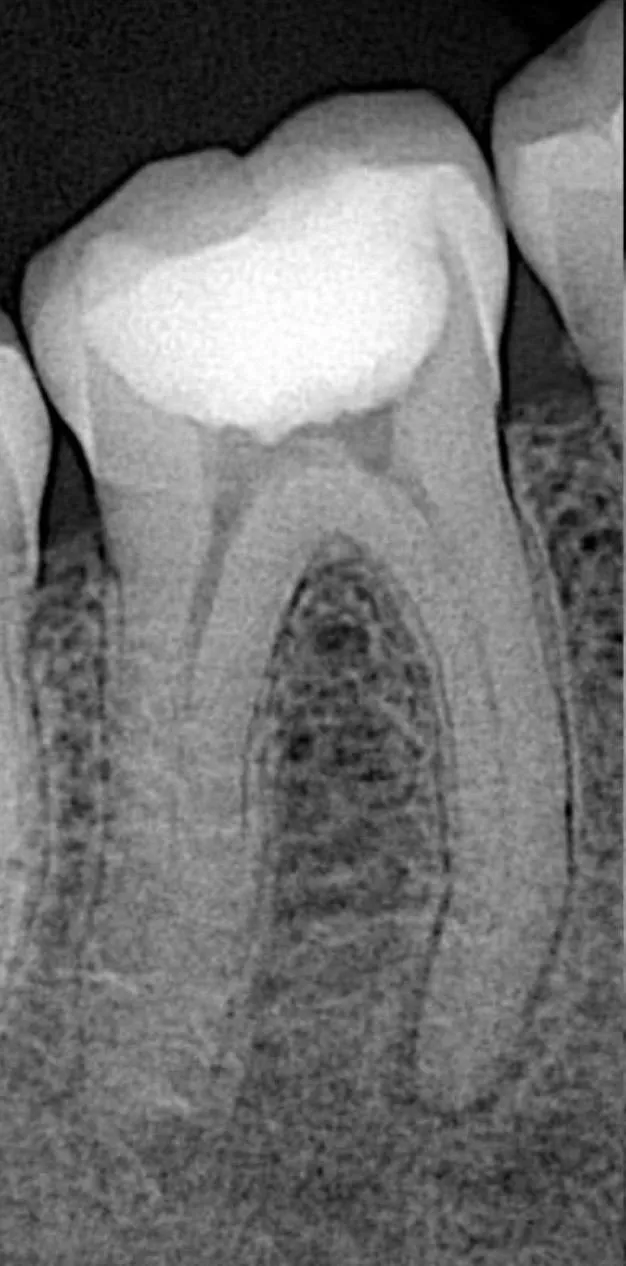

قبل

بعد